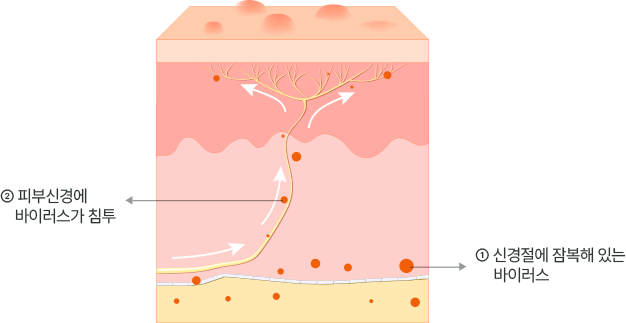

대상포진 발생 원인

수두-대상포진 바이러스는 감염 이후 완전히 사라지지 않고 신경절에 잠복해 체내에 남아있다가

과로, 스트레스, 수면부족 등 요인에 의해 발병합니다.